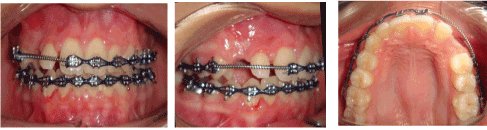

0.022 slot Roth brackets had been bonded on all upper and lower teeth except #12 which acted as a free body initially till the canine had been moved away from its root (Figure 3). After 6 months of alignment, space started to be created for the canine using opening coil spring (0.010 x 0.035 inch) (Figure 4). The first stage of surgery was planned to be VISTA technique in order to move the canine horizontally and to situate the canine crown directly under its socket using the microimplant (MI) (Figures 5 and 6). During surgery, all the bone distal to the canine crown till its CEJ which is in the way of its movement had been removed. A microimplant from (Ormco) VectorTas of 2 x 8 mm had been placed in the infrazygomatic crest parallel to the upper right first molar (Figure 7). A lingual button bonded on the labial surface of the canine and connected to the microimplant via a power chain which was passing under the alveolar mucosa over the canine. The horizontal movement of the crown had been activated every month by cutting a hole from the power chain. A panoramic periapical radiograph A-B taken directly after MI placement and 3 months over that to control the movement of the canine (Figures 8 and 9). After 3 months of horizontal movement of the canine, the patient referred again for the 2nd stage of surgery where a full reflected flap performed in order to remove the old power chain and place new one which is directly connected to the main archwire (Figure 10). All the bone above the canine crown till the 2 mm from the alveolar crest had been removed in order to facilitate the tooth movement vertically. The main arch wire which is 0.017x0.025 Stst had been offset in the area between #12, 14 (Figure 11). This offset placed to help for keeping the canine root in the alveolar bone and avoid the labial tipping of the crown. A crimpable attachment with a hook fixed on the wire directly over the canine crown and a power chain connected directly from the lingual button to the hook (Figure 12). The vertical movement of the crown had been activated every month by cutting a hole from the power chain. After the canine came out of the soft tissue a bracket bonded and thin wire placed in its slot with a sequence of 0.12 Niti, 0.14 Niti, 0.16 Niti, 0.16 x 0.22 Niti, 0.16 x 0.22 Stst, 0.17 x 0.25 Niti and 0.17 x 0.25 Stst. Canine root torque had been checked after its reaching to the occlusal plane and found that no need for any adjustment since it is similar with the opposing canine root eminence (Figure 13). After 24 months of active treatment, all appliances were debonded (Figure 14). Orthopantogram, lateral cephalography and periapical radiograph had been taken to record as a baseline for future follow up and assessment. Clear overlays delivered for both arches as retainers with proper instructions (Figure 15).

Figure 11. Intra oral photos show the vertical traction #13

Figure 12. Intra oral photos with a button which attached on the canine to be shown through the soft tissue as #13 started to erupt

Figure 13. Bracket bonded on #13 after its eruption and starting with its levelling and alignment

Figure 14. Intra oral photos of post orthodontic treatment